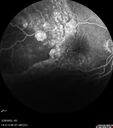

58 year old female The patient noticed decreased vision in the right eye about 2.5 months ago. (you may want to omit this initially -> ) 3 months ago she found a lump in her breast and had stage IV cancer which had spread. It is in her bone, lung. She is starting radiation tomorrow on a couple of vertebrate. Medical Hx: (Onset: 3/28/2023). Breast Cancer Stage 4. Hypertension, Systemic. Surgical Hx: Tonsillectomy. C-Section. Systemic Meds: Propranolol Hydrochloride, 80 mg oral tablet qday. PROCHLORPERAZINE 10MG qday. ANASTROZOLE 1 mg ORAL TABLET, FILM COATED [Anastrozole] qday. Dexamethasone 400 MCG/0.1ML PFS qday. VA OD: Dcc20/200 VA OS: Dcc20/63 IOP: TP: OD:12 OS:15 Put breast cancer history here: Had 10 sessions of radiation to the right eye starting 4/2023 and ending 04/26/23. Also - 4/2023 - kisqali and letrosole (forever drugs) 12/12/23 - Retinal detachment almost completely resolved – Exudative RD took 8 months to resolve. – VA improved from 20/200 to 20/40 (last visit)

Choroidal Metastatic Breast Cancer with Exudative Detachment109 views58 year old female presented with 20/200 vision. Had 10 sessions of radiation and tumor shrank. The exudative detachment took almost a year to resolve. The vision improved to 20/40.00000